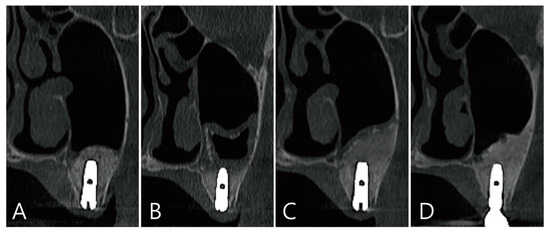

CBCT was taken immediately after MSA, one week after surgery, and before the uncovering procedure (Figure 3A–C). On the coronal image of the CBCT taken immediately after surgery, it was confirmed that MSA and implant placement were performed at the same time, and no dislocation of the bone graft particles was observed (Figure 3A). On the coronal image of the CBCT taken one week after surgery, severe grafting voids occurred on the upper part of the implant apex, and the maxillary sinus membrane was also thickened severely (Figure 3B). On the CBCT taken just before the uncovering procedure, the grafting void decreased in size, but a radiolucent image resembling SCC was observed. The thickened maxillary sinus mucosa was also reduced (Figure 3C). The grafting void was removed and a prosthesis was delivered. On the CBCT taken 6 months after the prosthesis was delivery, the radiopacity of the removed grafting void site was increased (Figure 3D).

Figure 3. (A) Coronal image of the CBCT taken immediately after surgery. There was no perforation of the maxillary sinus membrane and no leakage of the bone graft substitute; (B) coronal image of the CBCT taken one week after surgery. A severely enlarged grafting void was observed above the implant apex, and the ostium was obstructed due to severe membrane thickening; (C) coronal image of the CBCT taken 6 months after surgery. Although the grafting void was reduced in size, it appears similar to the SCC; (D) the radiopacity of the removed grafting void site was increased in the CBCT images taken 6 months after the prosthesis was delivered.